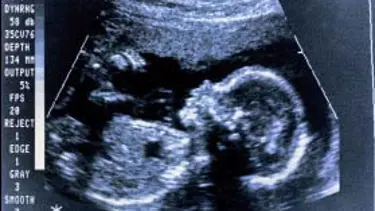

Ceninin kalp atışı, kan hücresi oluşturuyor

Ana rahmindeki ceninin kalp atışının yarattığı mekanik baskının, kan hücreleri ve kan dolaşım sisteminin oluşumunu sağladığı ortaya çıktı.

Araştırmada, kök hücrelerinin kan hücrelerine ve dolaşım sistemine dönüşmesini sağlayan en önemli faktörün, kalp atışının oluşturduğu biyomekanik baskı olduğu saptanırken, araştırma, uzun süredir bilim adamlarının kafasında yer eden "Neden hem insan, hem de hayvan embriyosunda henüz kana ihtiyaç olmadığı erken dönemde kalp atmaya başlıyor?" sorusunu da aydınlatıyor.